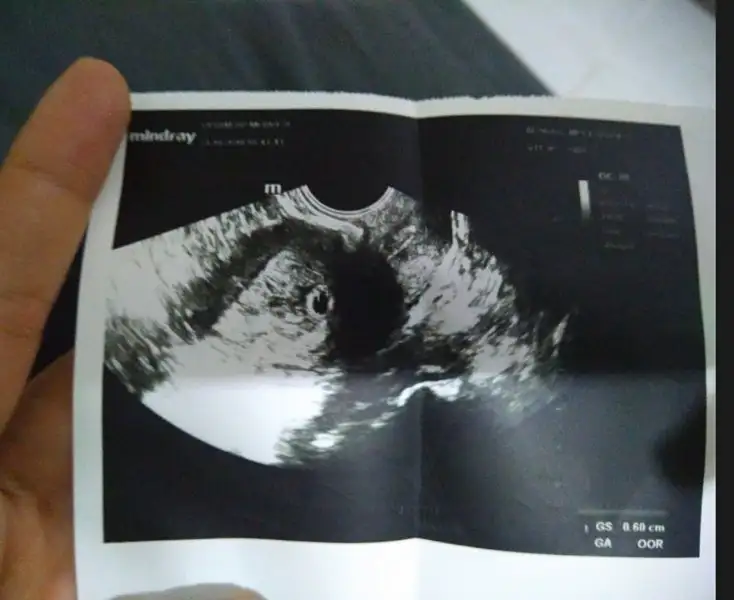

evet var eğer iş yerimde unutmamışsam :)Ultrason görüntüsü var mı canım

buyur canımevet var eğer iş yerimde unutmamışsam :)

Çokkkkk çok teşekkür ederim Allah razı olsun içimi rahatlattınız:)He gördüm 0.65 çıkmış

Canım sende bizim gibi hamile imzası oluştursana :)İyi MâşâAllah benimde Pazartesi göründü ama daha çok küçük dedi sizin keseniz kaç mm'di bi bakabilir misiniz zahmet olmazsa biraz evham yaptım beni haftaya Çarşamba tekrar çağırdı İnşâAllah herşey yolundadır